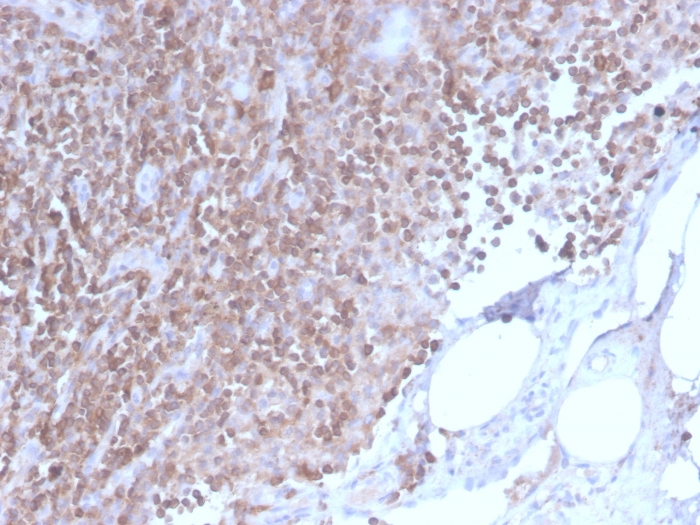

Product information "Anti-CD3e (T-Cell Marker), recombinant antibody, clone C3e/2858R"

Formulation: Purified Ab WITHOUT BSA at 1.0mg/ml. Cellular Localization: Cell membrane. Positive Control: Jurkat cells. Tonsil and lymph node. Chromosome Location: 11q23.3. Protein Function: Part of the TCR-CD3 complex present on T-lymphocyte cell surface that plays an essential role in adaptive immune response. When antigen presenting cells (APCs) activate T-cell receptor (TCR), TCR-mediated signals are transmitted across the cell membrane by the CD3 chains CD3D, CD3E, CD3G and CD3Z. All CD3 chains contain immunoreceptor tyrosine-based activation motifs (ITAMs) in their cytoplasmic domain. Upon TCR engagement, these motifs become phosphorylated by Src family protein tyrosine kinases LCK and FYN, resulting in the activation of downstream signaling pathways (PubMed:2470098). In addition of this role of signal transduction in T-cell activation, CD3E plays an essential role in correct T-cell development. Initiates the TCR-CD3 complex assembly by forming the two heterodimers CD3D/CD3E and CD3G/CD3E. Also participates in internalization and cell surface down-regulation of TCR-CD3 complexes via endocytosis sequences present in CD3E cytosolic region (PubMed:10384095, PubMed:26507128). In addition to its role as a TCR coreceptor, it serves as a receptor for ITPRIPL1. Ligand recognition inhibits T-cell activation by promoting interaction with NCK1, which prevents CD3E-ZAP70 interaction and blocks the ERK-NFkB signaling cascade and calcium influx (PubMed:38614099) [The Uniprot Consortium]

| Application: | IHC, WB |